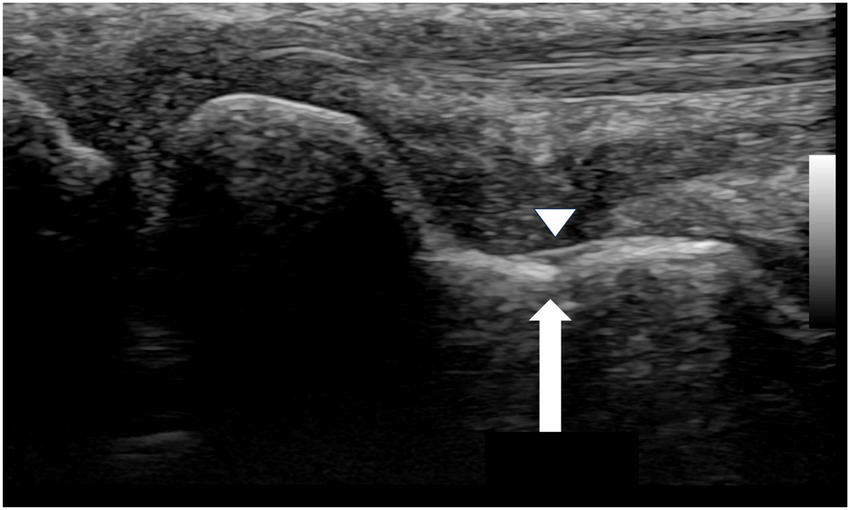

This created a diagnostic dilemma, as the radiographic findings alone could have been misinterpreted as a persistent non-union. In contrast, the follow-up ultrasound examination provided a definitive assessment. It revealed early callus formation and restoration of cortical continuity across the scaphoid waist. Most critically, a repeat dynamic stress examination was performed, which revealed no widening of the former fracture site under stress, confirming that mechanical stability had been achieved (Figure 4).

Figure 4

Follow-up ultrasound image of the waist region of the scaphoid (September 1, 2020). The white arrow indicates restoration of cortical continuity and formation of a bony bridge over the fracture site. The arrowhead demonstrates the bony callus formation.

This starkly contrasted with the ambiguous radiographs, demonstrating that the fracture had healed into a stable fibrous union with sufficient integrity to prevent micromotion, thereby allowing for a confident conclusion to the treatment plan.